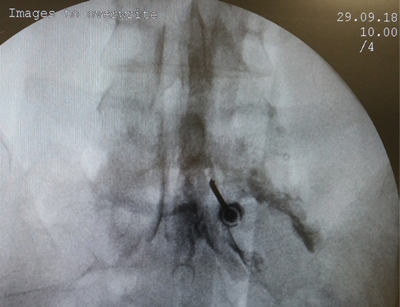

Figura 2